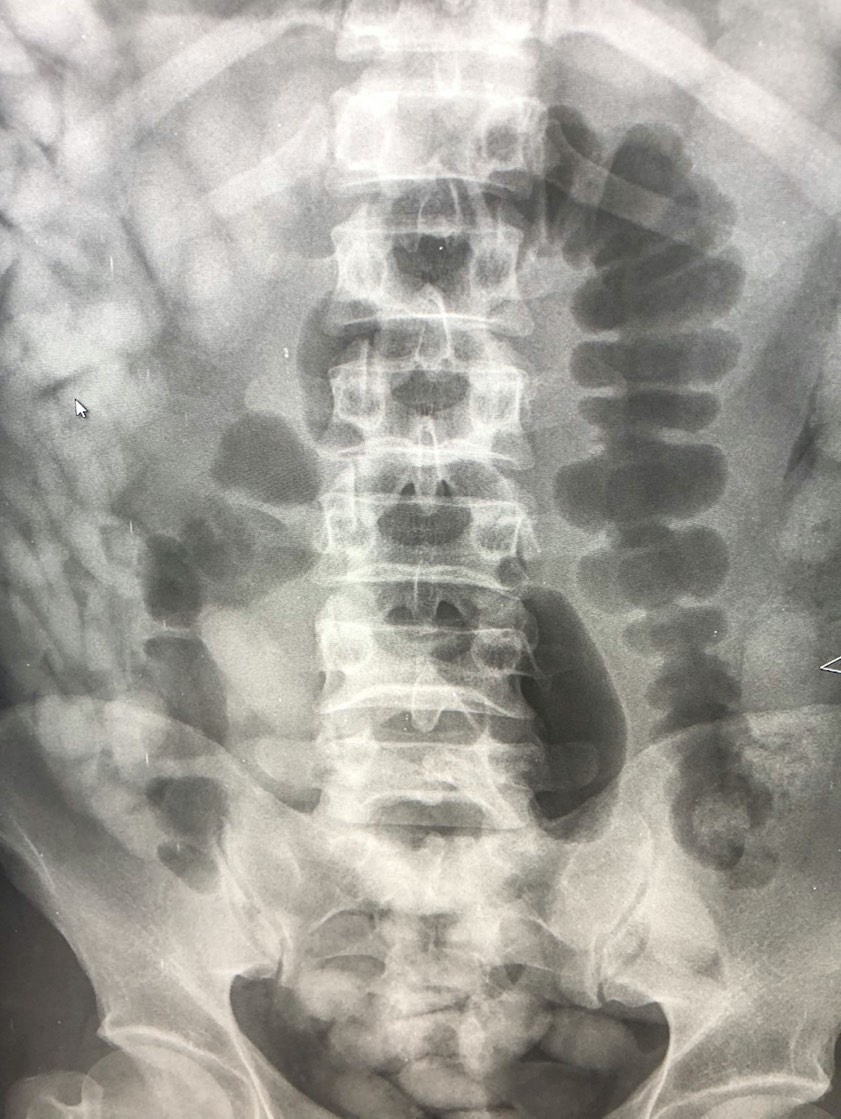

"Das Röntgenbild bestätigte den Verdacht der Zöllner. Im Laufe des Tages kamen 97 Behältnisse mit Kokain zum Vorschein, die über den natürlichen Weg ausgeschieden wurden", berichtete heute Marie Müller, die Pressesprecherin des Hauptzollamts München. Insgesamt sei rund ein Kilo Kokain sichergestellt worden. Gegen den Mann sei auf Antrag der Staatsanwaltschaft ein Haftbefehl erlassen worden. Die weiteren Ermittlungen habe das Zollfahndungsamt München übernommen.